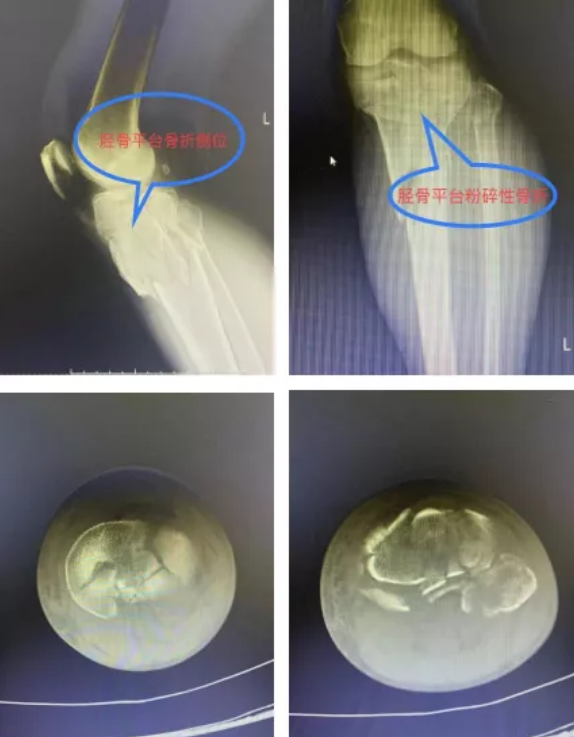

到达医院后,关节创伤骨科值班医生袁文泽和主治医师刘超迅速接诊,在查看伤情后随即安排检查,X光结果提示:左膝胫骨平台内外后三个方向塌陷骨折,需要手术治疗。经过一个星期的跟骨牵引、消肿、止痛抗凝等治疗,吴师傅伤情稳定,10月18日,关节创伤骨科主任王显勋根据伤者具体情况,选择为其进行内外后三个方向钢板固定术,通过胫骨平台内外侧两块钢板巧妙恢复胫骨平台关节面的平整,同时将骨折固定牢靠,两个小时后吴师傅被顺利推出手术室。

(术中、术后X光片)